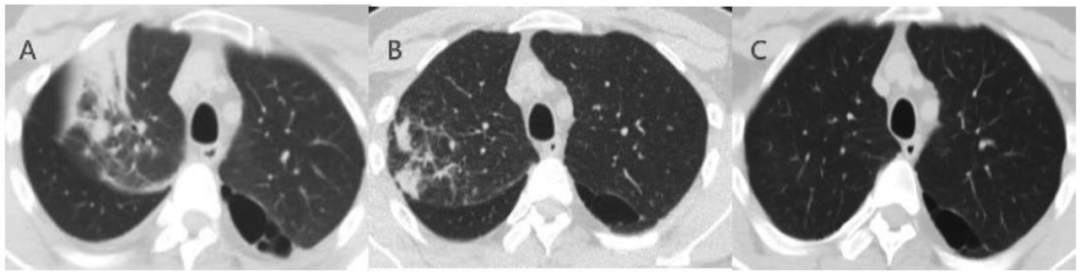

后续:热退,顺利出院。6 周后复查 CT 左下肺渗出基本吸收(图 2)。

图 2 胸部 CT 左下肺渗出(图 A、C)经治疗后出院,6 周后复查 CT 已明显吸收(图 B、D)。

图 3 患者胸部 CT。入院时 CT(A)示右肺中叶实变伴炎性渗出,伴气管充气征,左下肺 GGO;入院治疗后第 7 天复查 CT(B)示实变与 GGO 有减少;2 个月后复查 CT(C)已完全吸收。